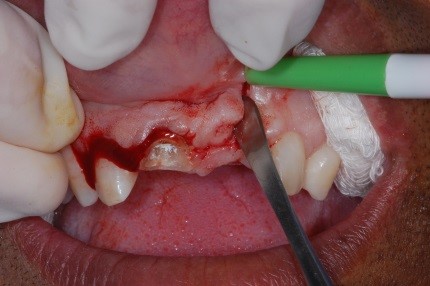

O retalho escolhido foi de um paciente. A incisão foi efetuada com lâmina de bisturi nº 15. O retalho foi elevado. Foi realizada a osteotomia com broca de alta rotação da série 700, para ter acesso à região periapical. A lesão foi curetada com curta.

Com a broca foi realizada uma apicectomia e foram removidos 2 mm de ápice. A cavidade para retrobturação foi preparada com broca esférica, sempre sob irrigação com soro fisiológico, e então se realizou retrobturação.

O material retrobturador utilizado foi o MTA. Após a condensação do material na cavidade, removeram-se os excessos com uma cureta periodontal.

- Figura 8 – Descolamento do retalho.

- Figura 9 – Descolamento do retalho.